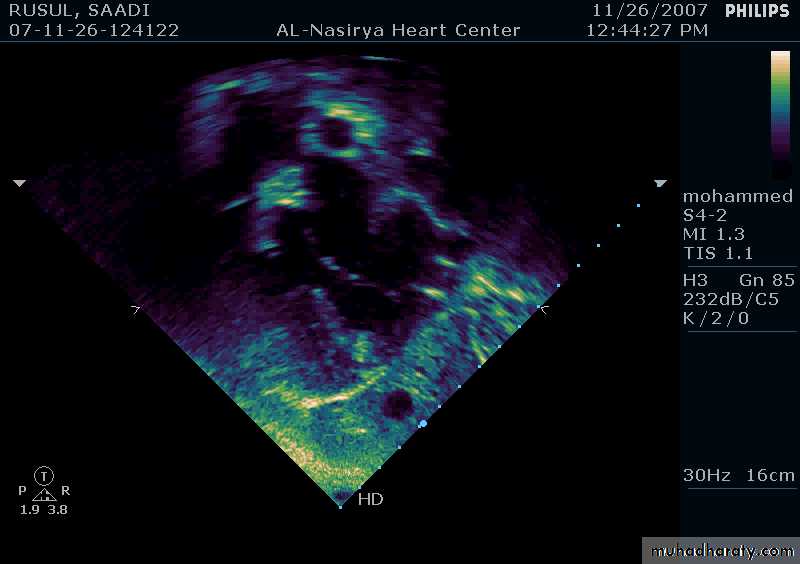

33Echocardiography & TEE

Shows the size of the defectThe direction of blood flow

The pulmonary artery pressure34

Ostium Primum ASD

37

38